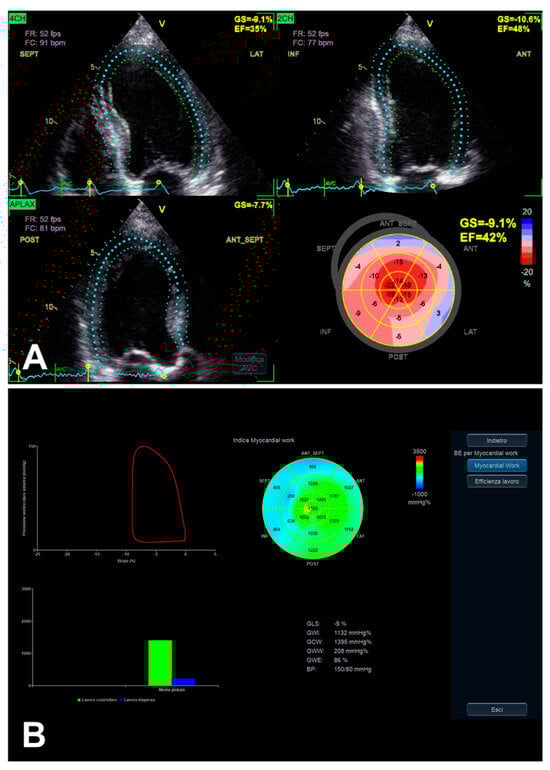

3.1. Left Ventricular Global Longitudinal Strain

3.3. Left Ventricular Myocardial Work